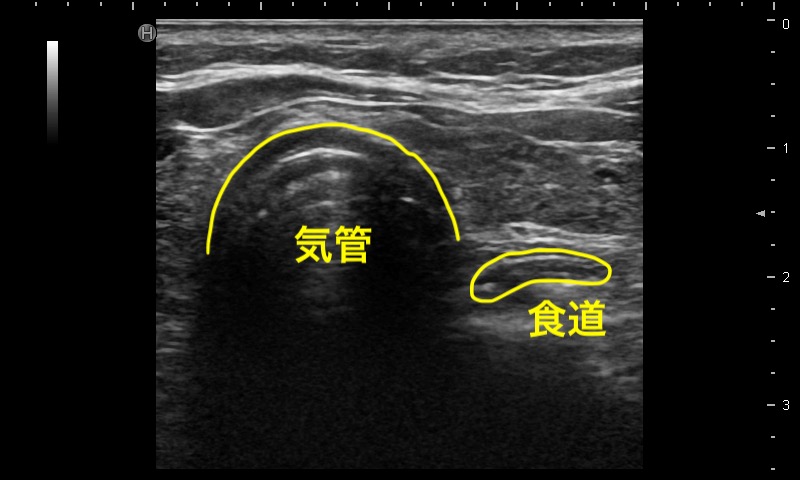

気管挿管(食道挿管)

バイタルサインのある患者での気管挿管の確認で最も信頼性が高いのはEtCO2の検知であるが、気道エコーにも同等の検出精度がある。通常、気管挿管の前後では描出像に変化がない(Single tract sign、下図左)が、食道挿管では挿管後に輪状構造物が食道内(多くは気管の左側、画面上は右側)に出現する。この所見はDouble tract sign(下図右)とよばれ、食道挿管を強く示唆する。バイタルサインのない患者では、気管挿管後もEtCO2が低値を示すことがあるが、気道エコーでは非CPA患者と同様な所見が得られる。(関連動画:#55, #69)